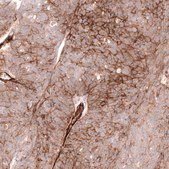

Anti-MCAM antibody produced in mouse

Prestige Antibodies® Powered by Atlas Antibodies, clone CL12855, purified by using Protein A, buffered aqueous glycerol solution

immunohistochemistry: 1:1000-1:2500